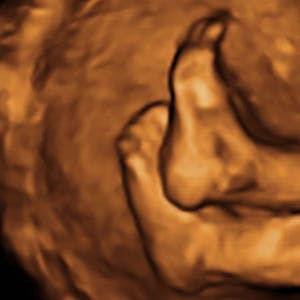

Gravid

Vi gør en dyd ud af at klæde dig godt på både før, under og efter din graviditet. Vi ved, at der kan komme mange spørgsmål til din graviditet, fødsel, amning, din babys udvikling og mange flere emner, derfor har vi samlet guides, tips & tricks samt læsernes egne fortællinger i dette gravid univers.